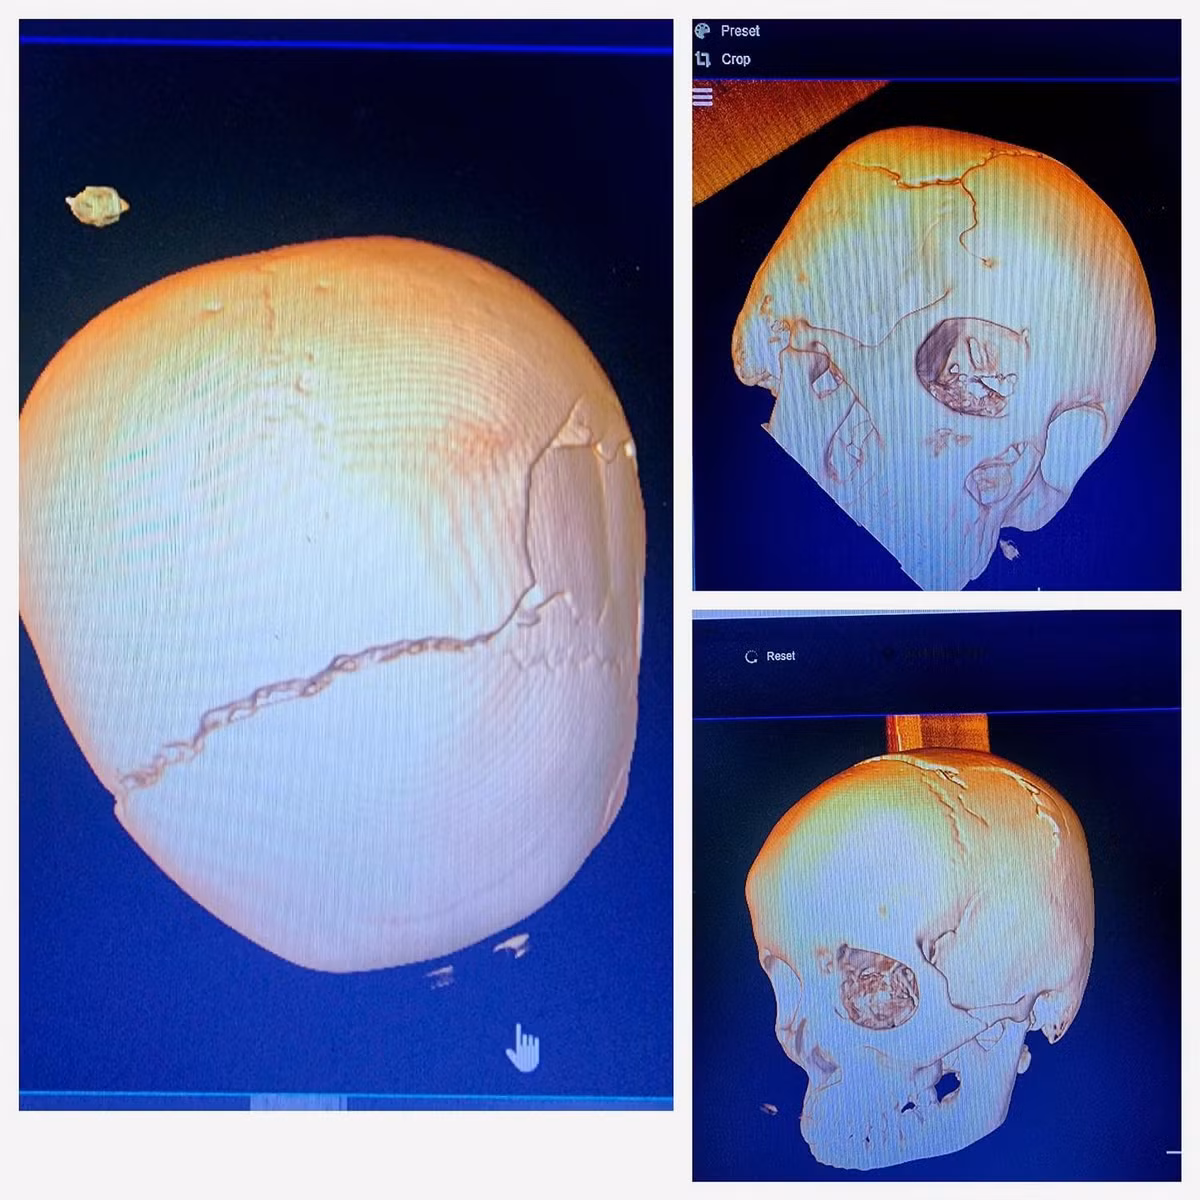

Khi nhập viện, bệnh nhân trong tình trạng hôn mê sâu, chẩn đoán vỡ sọ hai bên, dập não và tụ máu ngoài màng cứng với lượng lớn ở bên trái.

Hình ảnh sọ vỡ trên phim chụp - Ảnh BVCC